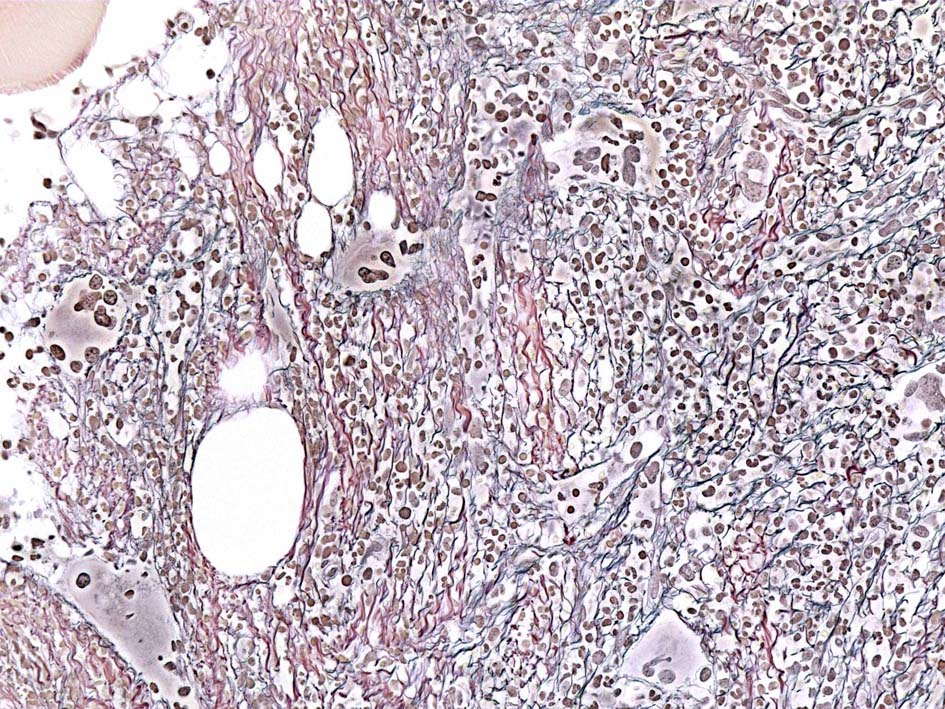

Case01; Meylofibrosis, overt fibrosis

77year-old female. 40歳時polycythemia veraと診断されていた.

[注] この症例は詳細は不明であるが, 過去にPVと診断されているため, PVに伴う二次性のmyelofibrosisの診断になる.

黒染する弾性線維の増生のほか, 赤く染まる膠原線維の増生が確認される. MF-2 fibrosis. 鍍銀染色の核染色をすると膠原線維の赤染がわからなくなるので行わない.